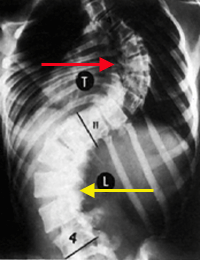

و كذلك بالأشعة يمكن معرفة ما إذا كان الجنف (الإنحناء) بنيوي أو مُعاوض (تعويضي) Compensatory Curvature , الإنحناء المُعاوض يحدث نتيجة للإنحناء البنيوي ليتوازن الجسم. تُأخذ صورة أشعة للشخص و هو منحني جانبياً لليمين و أخرى و هو منحني جانبياً لليسار, مما يؤدي إلى إختفاء الإنحناء المُعاوض و لكن الإنحناء البنيوي يظل. و هذه الطريقة كذلك تفيد في معرفة مرونة العمود الفقري لدى المريض.

في الصورة, في حال الوقوف الجنف يكون صدري قطني أيسر, عند الإنحناء يساراً لا يختفي الإنحناء الصدري لأنه بنيوي , و لكن عند الإنحناء يميناً يختفي الإنحناء القطني مما يعني بأنه مُعاوض و ليس بنيوي.

الفقرات باللون الأحمر = الفقرات الصدرية و الفقرات باللون الأصفر= الفقرات القطنية.